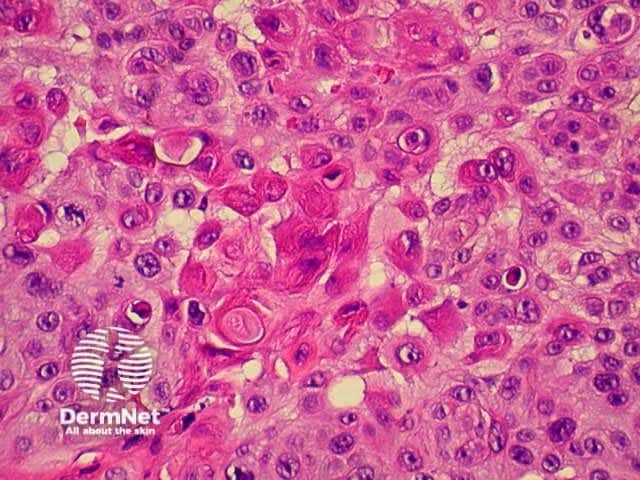

The histological characteristics of keratinocytic tumours are illustrated below.

Squamous cell carcinoma

SCC presents as an irregular keratinous nodule or a firm erythematous plaque, and frequently ulcerates. Histologically, atypical keratinocytes proliferate within the dermis.